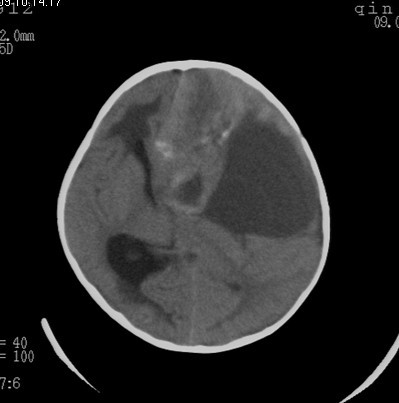

男  4岁  家长觉得反应迟钝来检查发现。

病史?脑疝都形成了,这家长也太马虎了。

考虑脑占位并出血,脑疝形成。

考虑左侧颞顶叶占位并出血,脑疝形成

考虑左侧颞顶叶占位并出血,脑疝形成!梗阻性脑积水

考虑左侧颞顶叶占位并出血,脑疝形成,梗阻性脑积水。

1)考虑左侧额颞顶叶肿瘤并卒中;建议行进一步检查。2)大脑镰下疝,左侧颞叶沟回疝。3)脑积水(梗阻性)。